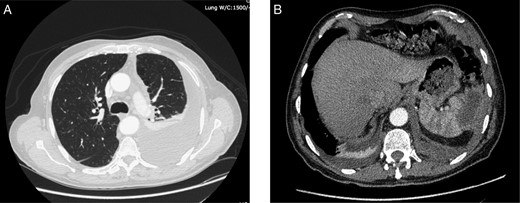

On admission, physical examination revealed normal vital signs and decreased breath sounds over the right pulmonary base as well as diffuse abdominal tenderness that was worse over the left hypochondrium. Blood culture samples as well as a complete blood count that revealed a normal hemoglobin and white cell count were taken. A CT scan confirmed the previously mentioned findings (Fig. 1). The patient was started on the same i.v. antibiotics he had been receiving (meropenem) and then taken to the operating room (OR) for video-assisted thoracoscopic lung decortication/pleurectomy. General surgery was then asked to assess the splenic abscess and, in consultation with interventional radiology, chose to treat conservatively. Two days later, the antibiotic regimen was simplified to i.v. ertapenem. After 4 days of this management, a new CT showed that the abscess had grown in size and had gas within it (Fig. 2). The decision was made to take the patient to the OR for a laparoscopic splenectomy.

CT scan taken on admission showing. (A) left-sided pleural effusion with empyema and septal loculations and (B) a subcapsular splenic abscess of approximately 5 cm × 2 cm × 3 cm with an approximate volume of 14 cc.